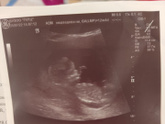

11 августа 2022 09:40 Сходила на УЗИ, то что тонус уже неделю частый ( показало что тонус приходящий тот есть то нет) щейка славо богу 43. И мне сказали пол у нас будет сын❤ как я рада вечером сообщу родным и мужу ?